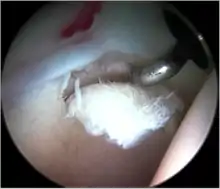

Figure 7. A complex labral tear. An arthroscopic probe is seen at the junction of the labrum and acetabular rim

Labral tears (see fig. 7)

Labral tears

The acetabular labrum is a fibrous structure, which surrounds the femoral head. It forms a seal to the hip joint,[15] although its true function is poorly understood. Recent evidence has demonstrated that this hydraulic seal is vital for maintaining stability of the ball and socket joint [16] and reducing contact pressures of the femur to the acetabulum.[17] The labrum has also been shown to have a nerve supply and as such may cause pain if damaged.[18] The underside of the labrum is continuous with the acetabular articular cartilage so any compressive forces that affect the labrum may also cause articular cartilage damage, particularly at the junction between the two, the chondrolabral junction. The labrum may be damaged or torn as part of an underlying process, such as FAI or dysplasia (shallow hip socket), or may be injured directly by a traumatic event. Depending on the type of tear, the labrum may be either trimmed (debrided) or repaired. Removing or debriding the labrum is becoming less popular as the latest research shows that results are more predictable in the long term if the labrum can be repaired. Various techniques are available for labral repair, mainly using anchors, which may be used to re-stabilise the labrum against the underlying bone, allowing it to heal in position.